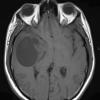

NEOPLASMS (GLIAL)

Glioblastoma, granular cell type (5)